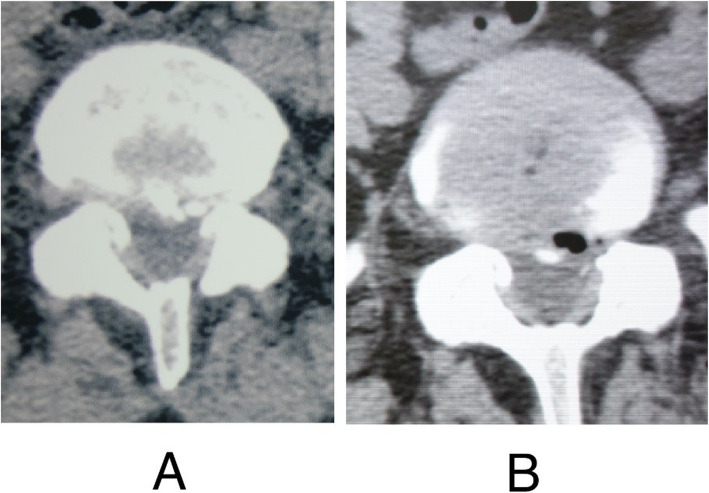

Before the surgery, patients received MRI to determine the herniated level and CT scan to confirm the presence of calcification. Posteroanterior and lateral X-rays were required to detect scoliosis or high iliac crest when the lower plate of L4 vertebral body was not higher than bilateral iliac crest. After operation, CT scan was undertaken to confirm the excision of calcification (Fig. 5). Postoperative MRI images were acquired to evaluate decompression outcome and exclude hematoma and dural sac rupture or spinal fluid leakage.

Fig. 5.

Preoperative and postoperative CT scan images of a 46-year-old female patient who had radiating leg pain for one month and received PTES. .a Preoperative CT scan image showed calcified herniation at L5/S1 level. b Postoperative CT scan image confirmed the removal of the calcification